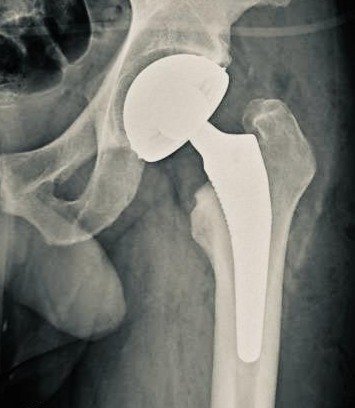

Reducción y pruebas de estabilidad

-La reducción suele ser fácil con simple tracción y rotación interna siempre y cuando las medidas de los componentes se asemejen a la cadera nativa.

-En pacientes que dejaron pasar mucho tiempo para recibir atención, o en caderas muy destruidas, y en aquellos que sólo se opera un lado, puede haber discrepancia en la longitud de la extremidad y esto dificultar a su vez, la reducción de la prótesis, es decir, meterla en su sitio.

-El reducir la prótesis siempre hacemos pruebas de estabilidad simulando movimientos forzados e incluso exagerados que el paciente podría hacer para asegurarnos de que la prótesis no se vaya a salir de su sitio (luxación).

-La prótesis total de cadera se llama TOTAL porque reemplaza fémur y acetábulo. En caso de sólo reemplazar fémur y colocar una copa móvil en el acetábulo sería una prótesis bipolar o de dos cabezas. Su indicación es en paciente seniles de baja demanda. Siempre las vamos a preferir a una monoblock (Thompson, AustinMoore, Lazcano), el precio no justifica el riesgo de artrocatadiasis secundaria o protrusión intrapélvica.

-Un buen sistema bipolar permite intercambiar cabezas de copas con vástagos tanto cementados como no cementados y tamaños de cabezas. Eso lo hace mas preciso pero más caro.

-En la foto se muestra un vástago cementado de revisión Reactiv y una copa Moonstone de Evolutis.

-Mas aún, por abordaje vía anterior se puede colocar una prótesis total de cadera de doble movilidad.

Prótesis total de cadera con inserto convencional fijo

Prótesis total de cadera con inserto móvil doble movilidad